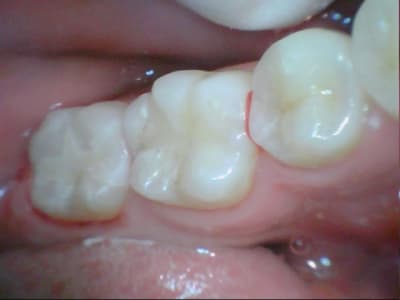

31/10/2011 à 18h09

tiens je me suis chronométré :)

28min :) lol

bon celui la etait un peu long, car provisoire collé au cvi cause durée avec le provisoire trop longue....

donc dur a déposer et obligé d'enlever les résidu de cvi aux US...

ceux qui font pas d'onlay vous proposez quoi là ?

patiente de 13 ans ...

heu spifen 400 c'est pas de la pub lol

Ca ressemble à un beau MIH avec un confrère qui a fait des trucs bizarres avec un amalgame.

Oui MIH déjà avec une belle récidive de carie. Je pense que dans un cas comme ça le compo est voué très vite à l’Échec...